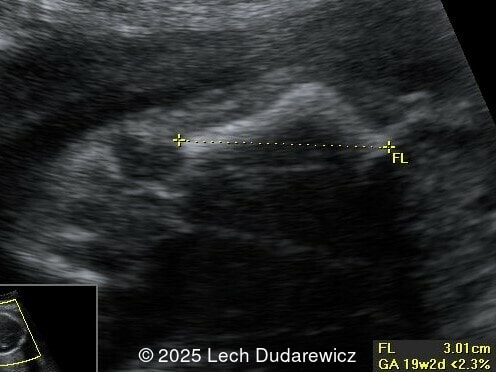

Image 1

Ultrasound revealed a single live fetus with 46,XY karyotype. Biometric measurements demonstrated discrepancies with the femur and tibia length lagging significantly at 19 weeks and notable shortening and bowing of the femur, tibia, and fibula. The findings were consistent with skeletal dysplasia.

Prenatal ultrasound is a crucial tool for early diagnosis, enabling appropriate counseling and perinatal management of campomelic dysplasia. Key skeletal abnormalities include significant shortening and bowing of long bones, particularly the femur and tibia. In a study by Mansour et al, the lower extremities are primarily involved with minimal bowing of the humerus, ulna, and radius. Bowing often presents with associated angulation, giving rise to the term "campomelia," meaning bent limbs in Greek. Hypoplastic iliac bones and scapulae are hallmark features, while rib anomalies such as deformities or reduced number, typically 11 pairs, may also be observed. Additionally, the chest may be narrow and bell-shaped. Cervical spine abnormalities, including excessive lordosis or kyphosis, are often present and may contribute to postnatal respiratory complications. These findings are important for risk stratification and delivery planning.